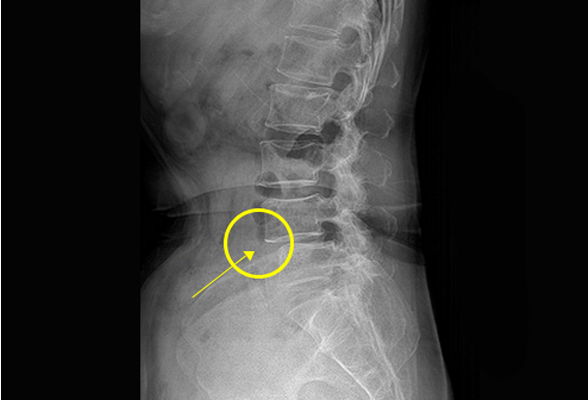

척추압박골절

척추압박골절이란 눌리는 힘에 의해 척추뼈에 골절이 발생하는 질환입니다.

특히 노년층이나, 폐경기 이후의 여성에게서 일상생활 중 가벼운 충격에도

척추 압박 골절이 유발됩니다.

비수술 치료 : 약물치료, 물리치료, 보조기 착용

수술치료 : 척추체성형술